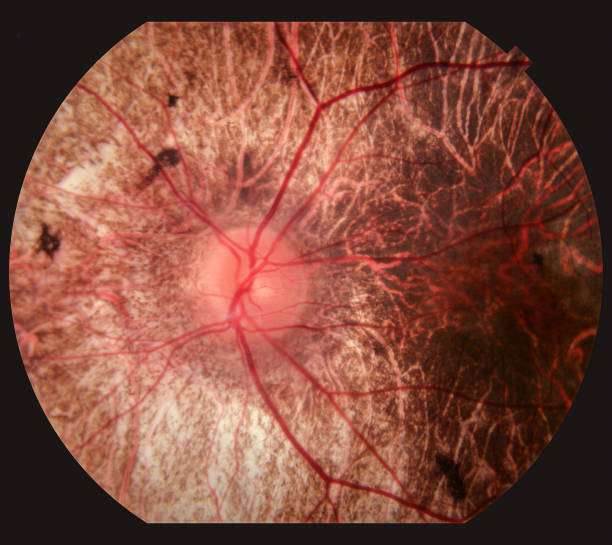

1) 결막염의 모습은?

이 질환에 걸리면 눈동자의 하얀 부분이 밝은 분홍색에서 불그스름하게 보이며 눈꺼풀은 부어오르거나 처져 있게 되기도 합니다. 감염되게 되면 눈에서 액체가 나와서 속눈썹과 눈꺼풀에 딱지를 촉발합니다. 그 결과 눈을 뜨기 힘들게 하였거나 잤다가 일어나면 눈곱이 수시로 생겨나게 해요.